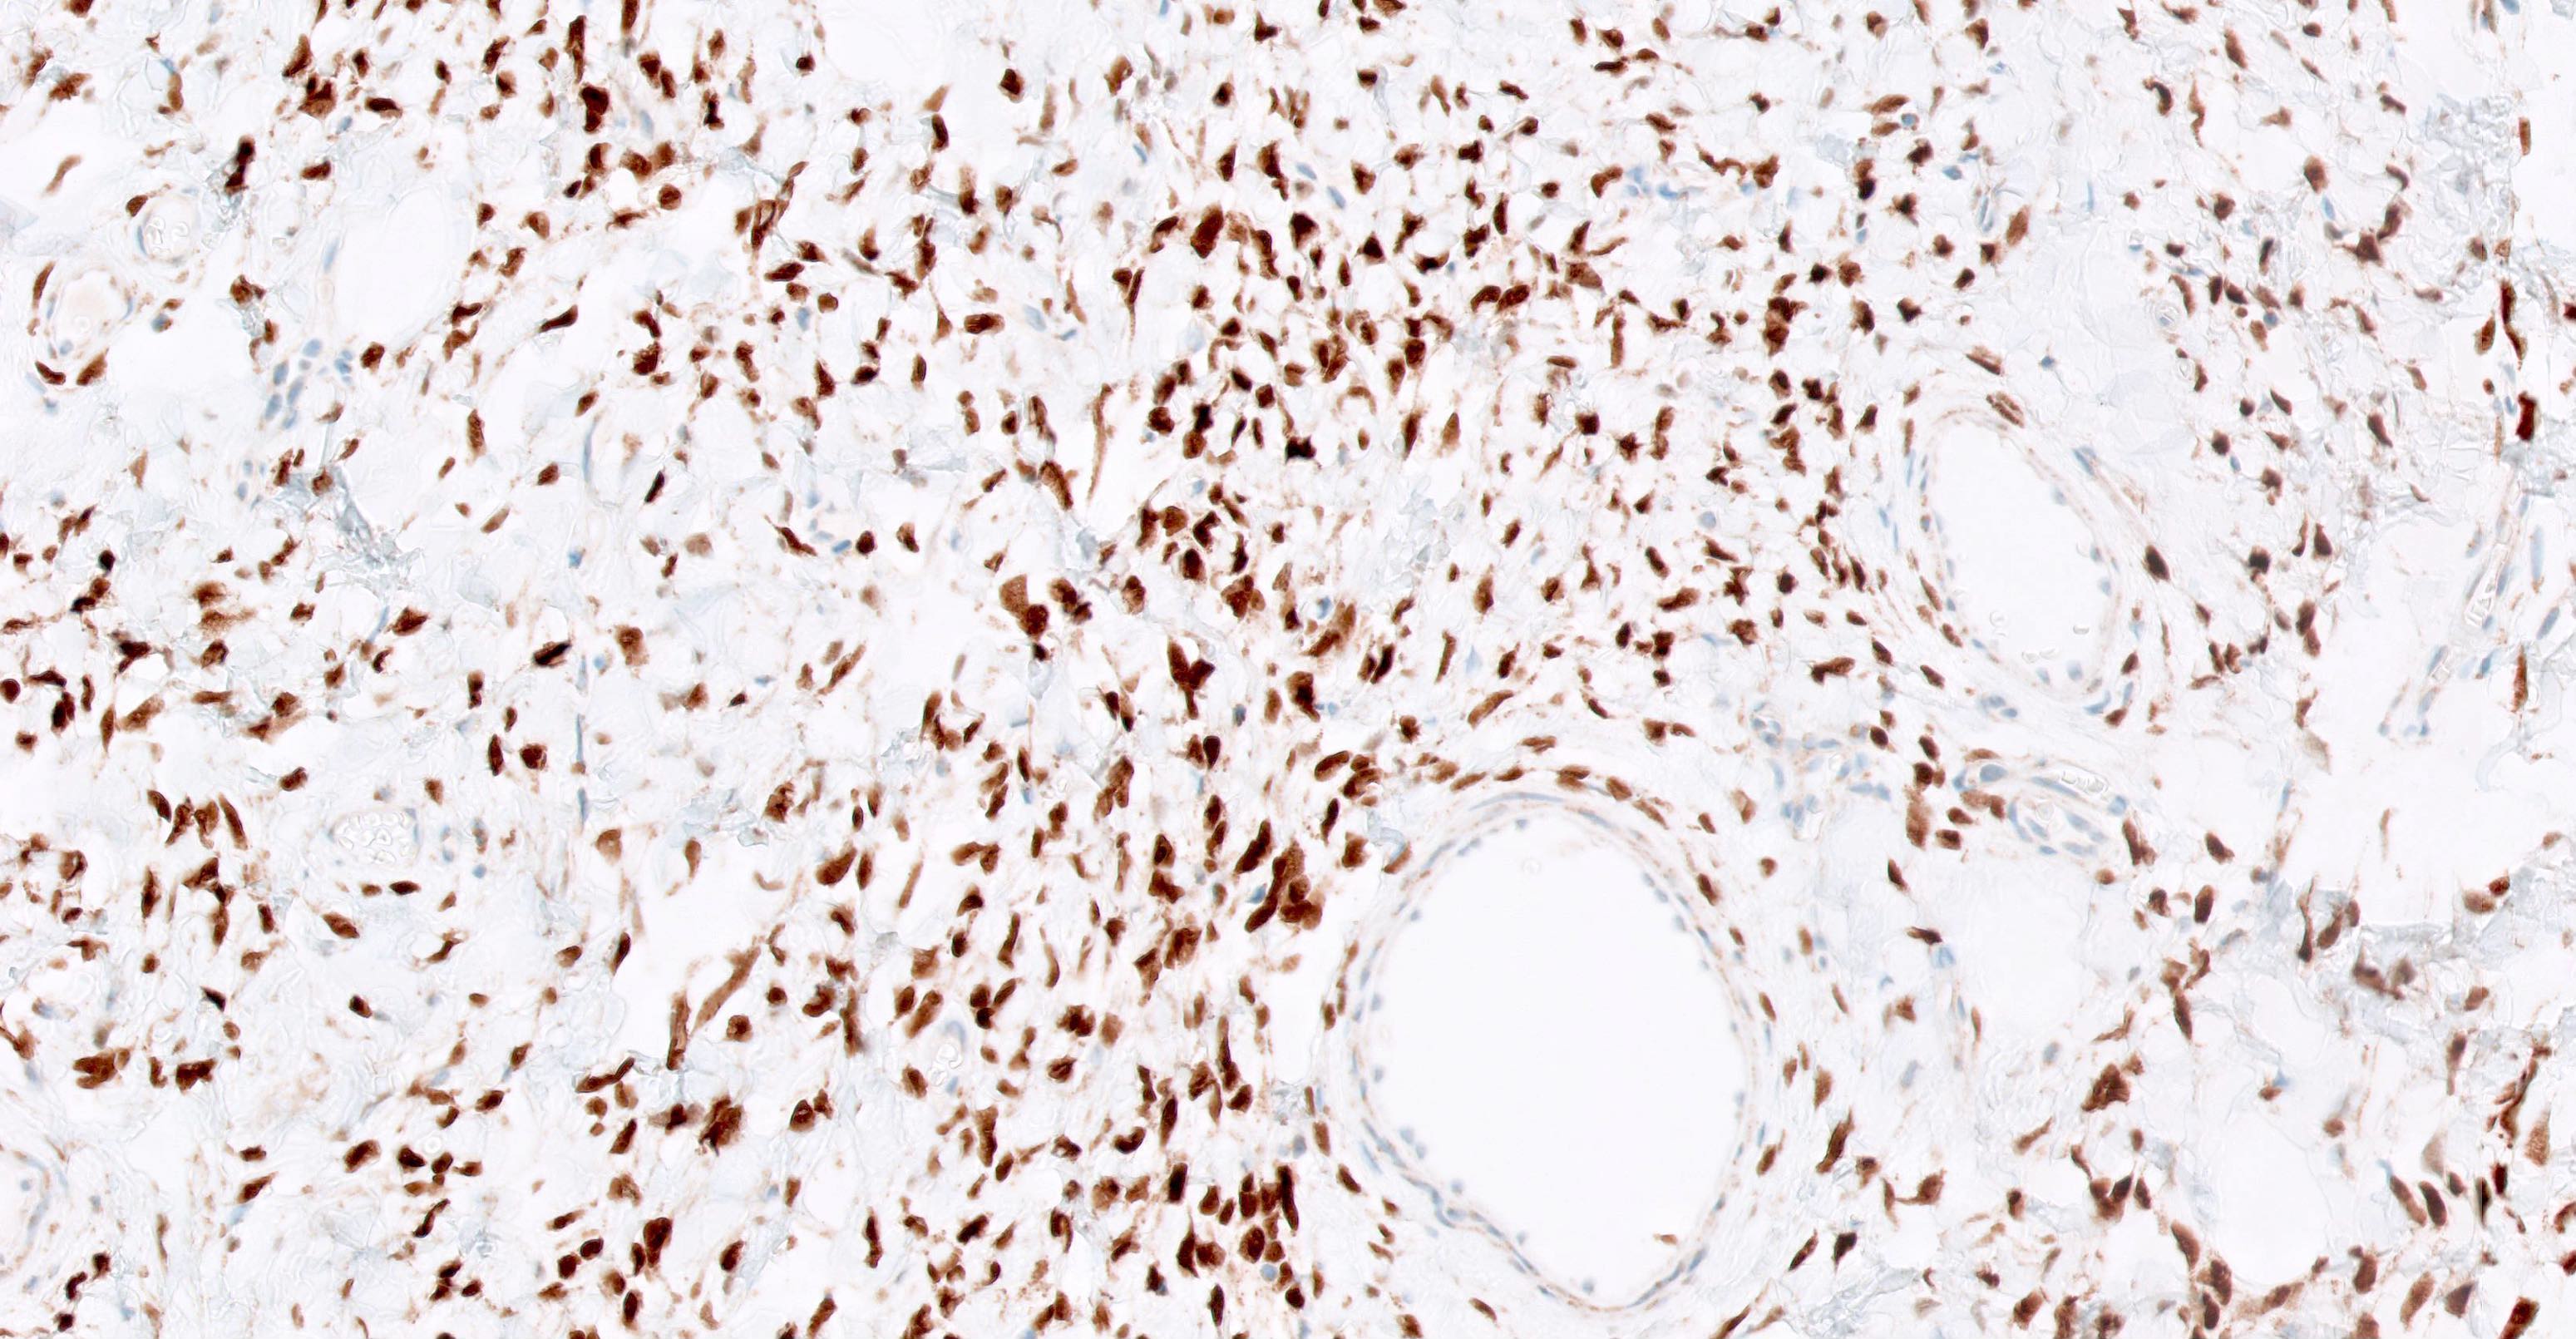

Microscopic (histologic) images

Positive staining - normal

- Solitary fibrous tumor (98 - 100%), regardless of morphology or site, typically strong and diffuse (Pathology 2014;46:389, Pediatr Dev Pathol 2018;21:389, Acta Neuropathol 2013;125:651)